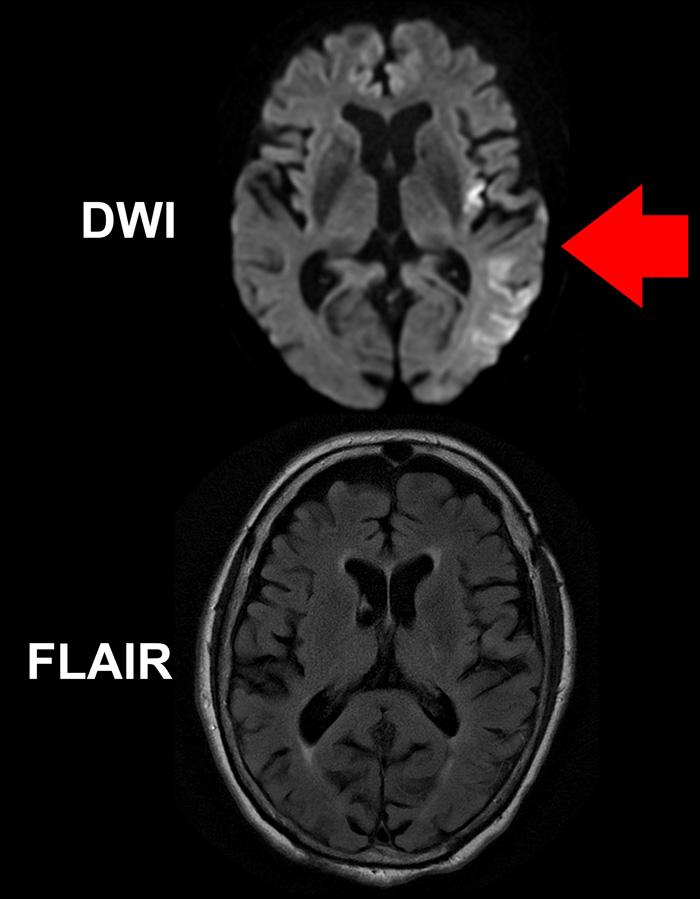

image: While a DWI MR image (top) of the brain of a stroke patient clearly shows areas of the brain impacted by the stroke (brighter areas indicated by red arrow), the FLAIR image below, taken at the same time, does not reveal obvious acute ischemic damage. The mismatch between the two images implies the patient was imaged within 4.5 hours of symptom onset.

In the current study, 80 patients with imaging-confirmed ischemic stroke of unwitnessed onset, who were less than 24 hours since they were last known to be well, were enrolled at 14 centers across the U.S. Study eligibility was determined by a mismatch between two types of MR imaging studies - FLAIR, which typically only shows stroke effects on brain tissue after several hours of reduced blood flow, and diffusion-weighted imaging (DWI), a technique first applied to stroke patients at the MGH-based Athinoula A. Martinos Center for Biomedical Imaging that is extremely sensitive to changes beginning in the first minutes or hours after stroke onset.

Study co-lead author Ona Wu, PhD, of the Martinos Center explains, "Brain tissue that is abnormal on DWI but not yet abnormal on FLAIR has been seen in patients that were 4 hours or less after known symptom onset. That discrepancy provides a snapshot of tissue evolution as the stroke progresses in the first few hours, and that is the pattern we used to select patients for treatment, since they were likely to be similar to patients with known symptom onset who have benefited from tPA. Essentially we used an MR Witness - the name of the trial - to identify patients who might be treated with tPA because their strokes had not progressed to the point of irreversible injury."